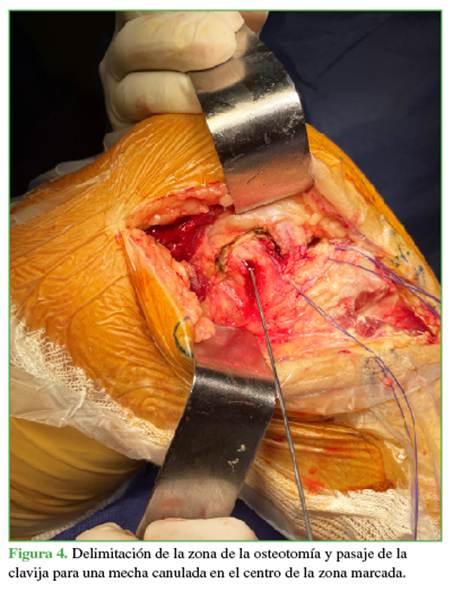

Además, al incluir la inserción del poplíteo, aumenta el área de visualización.2 En el centro del marcado, se perfora con una mecha canulada de 3,5 en dirección de 30° a proximal y 30° a anterior, dejando preparado el taco óseo para su reinserción (Figura 4).